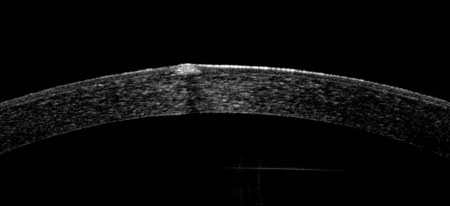

At Ocular Imaging we can accurately map the corneal thickness of normal, post operative and opacified corneas. The RTVue possesses sufficient resolution to allow routine measurement of epithelial thickness. For refractive surgery it can be used to screen out patients with forme fruste keratoconus by detecting focal thinning.

The pachymetry map offers coverage over the central 6mm diameter and automatically calculates the minimum thickness and the central thickness averaged over a central 2mm diameter circle.